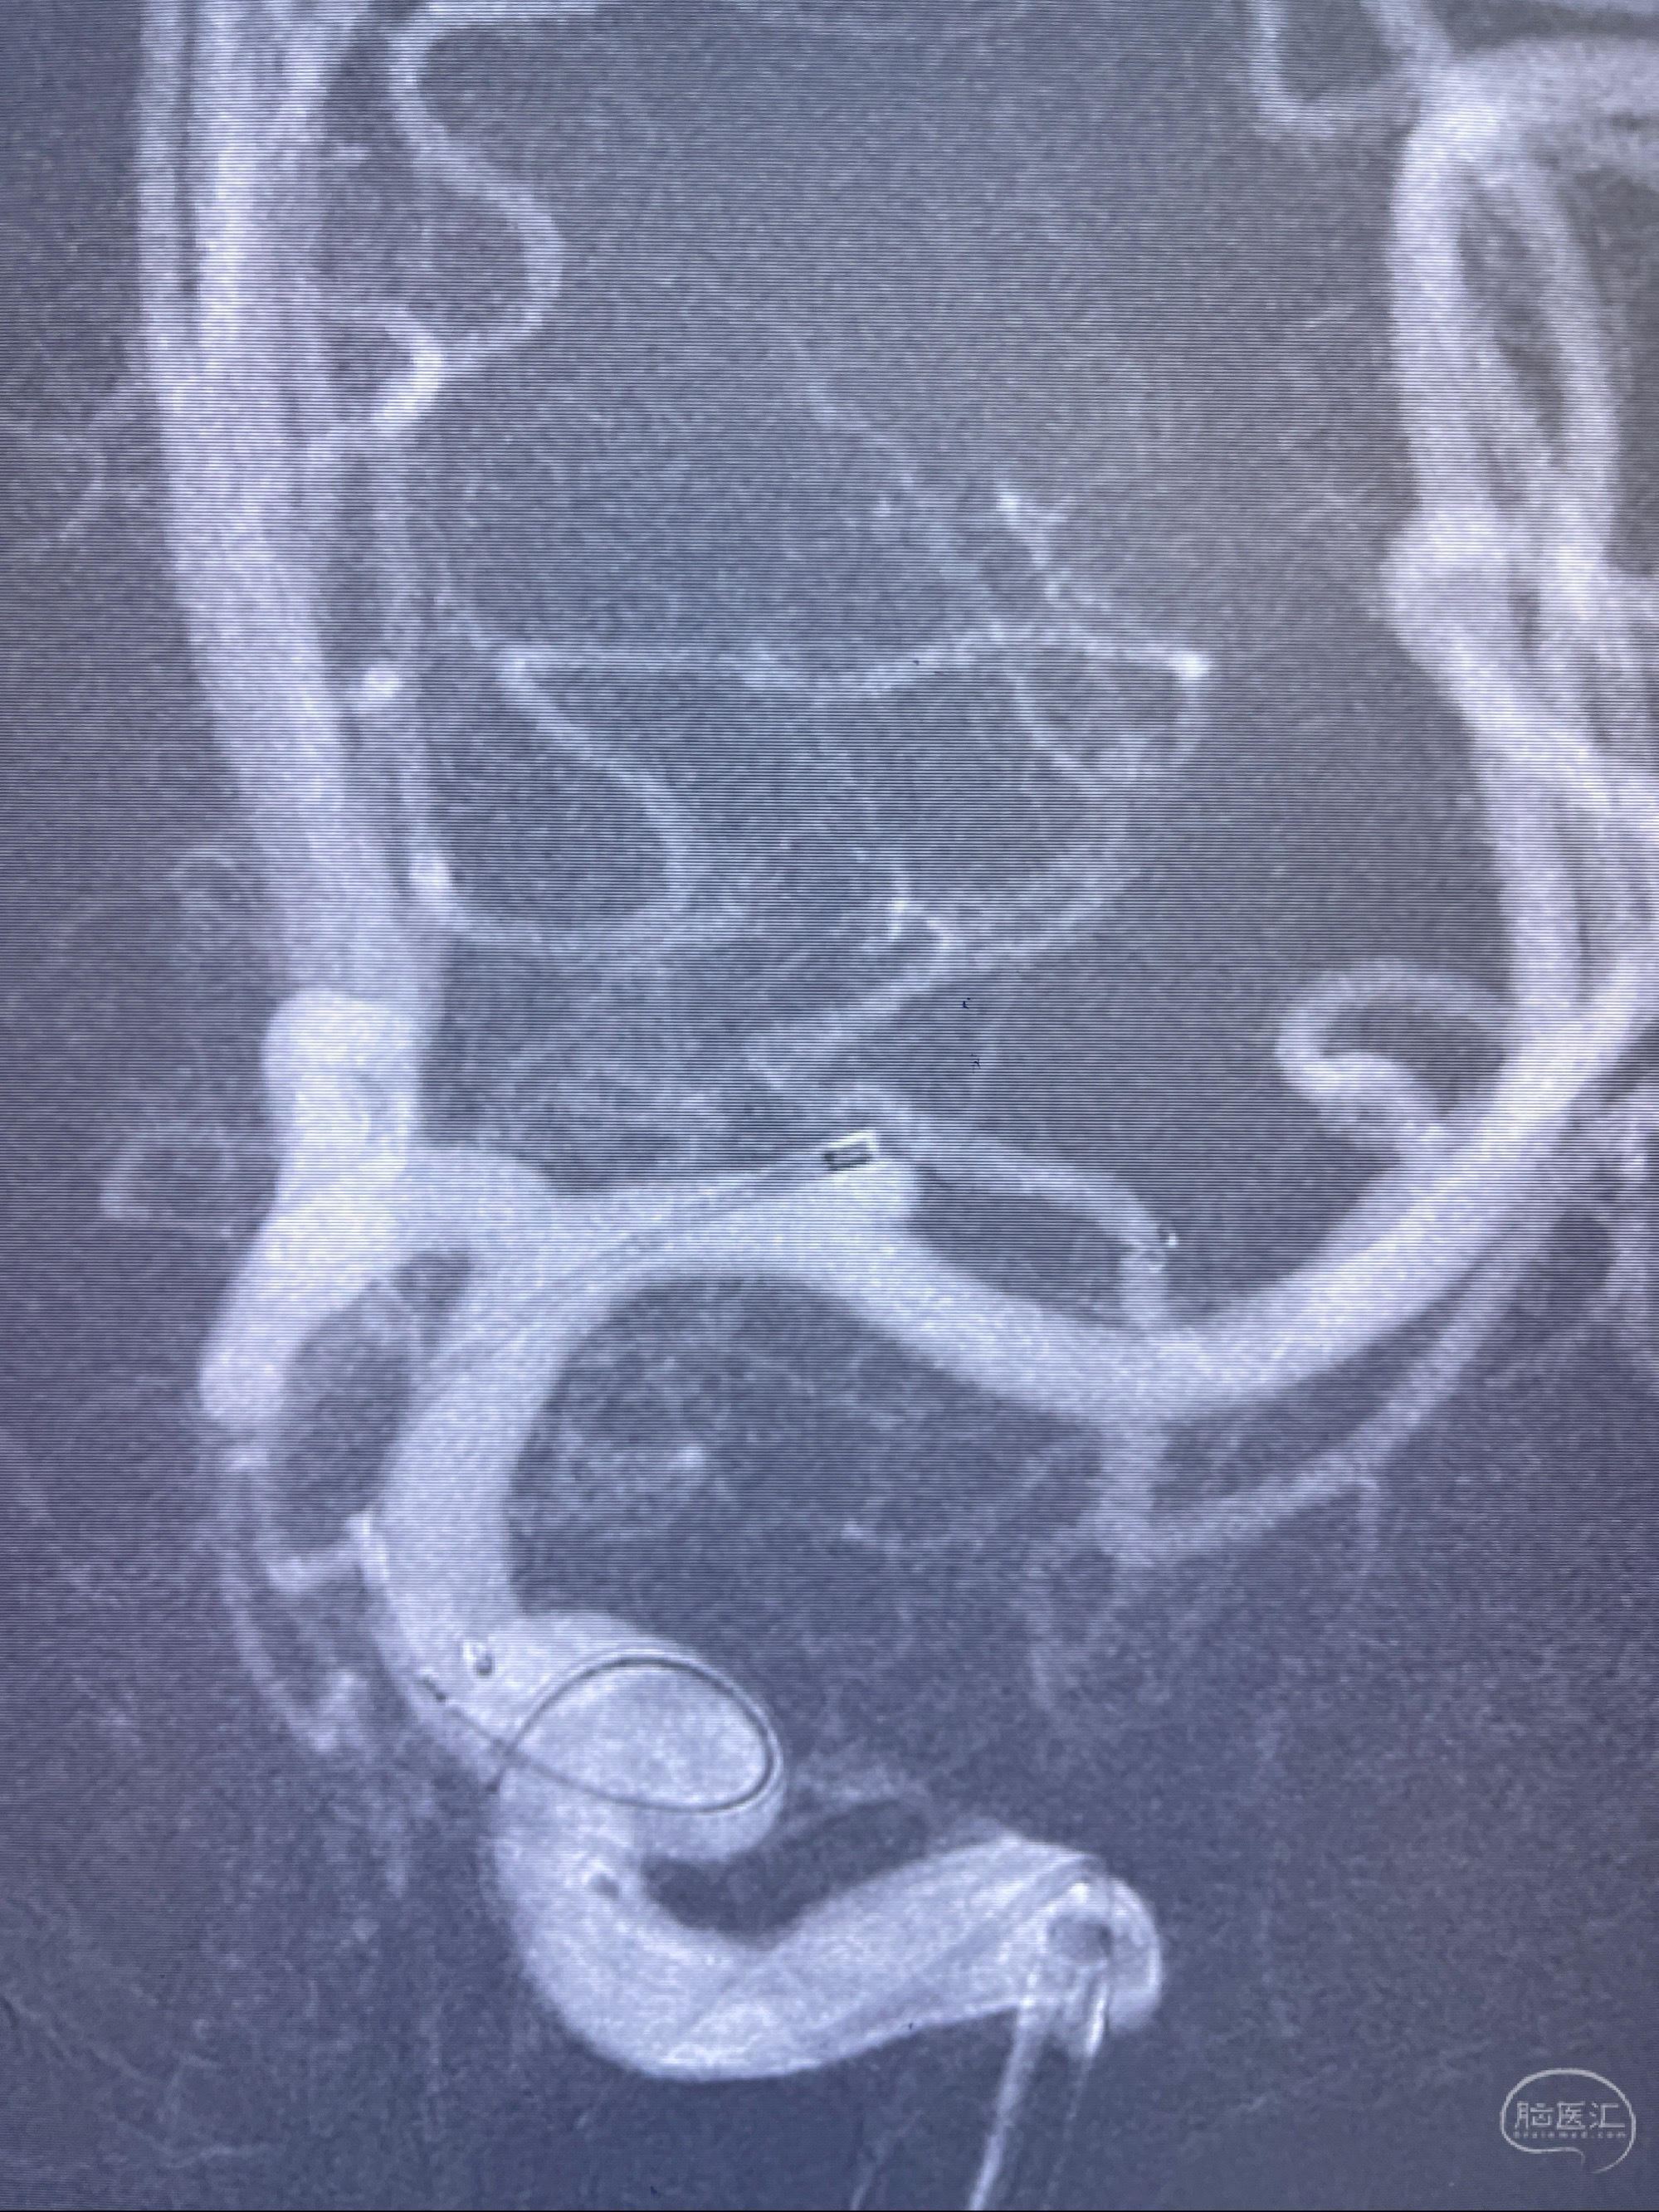

2023-08-14DSA:

左侧大脑中动脉动脉瘤,约2.6-2.8-3.4-2mm大小(瘤颈部、瘤体部、瘤高)

1.左侧大脑中动脉动脉瘤,约2.6-2.8-3.4-2mm大小(瘤颈部、瘤体部、瘤高)

2.外科手术夹闭or介入支架辅助栓塞